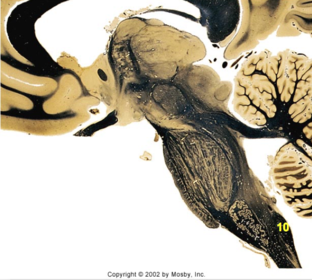

| Head of caudate | |

| Anterior commissure | |

| Thalamus | |

| Substantia nigra | |

| Optic tract | |

| Dentate nucleus | |

| Pons | |

| Longitudinal pontine fibers | |

| Uncus | |

| Superior cerebellar peduncle | |

| Red nucleus | |

| Corticospinal tract (dark) | |

| Pontine nuclei (pale) | |

| Transverse pontine fibers (dark) | |

| Inferior olive | |

| CTT | |

| Medial lemniscus | |

| Nucleus cuneatus | |

| Superior colliculus | |

| Inferior colliculus | |

| Optic nerve | |

| Cerebellum | |

| 4th ventricle | |

| Periaquaductal gray | |

| Dorsal funiculus | |

| MLF | |

| Mammillary body | |

| Pineal body | |

| Posterior commissure | |

| Thalamus |